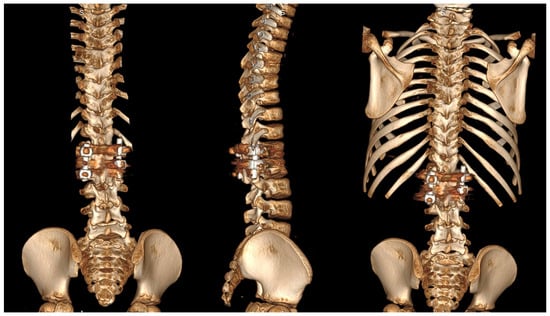

6.2. Advanced Imaging Modalities